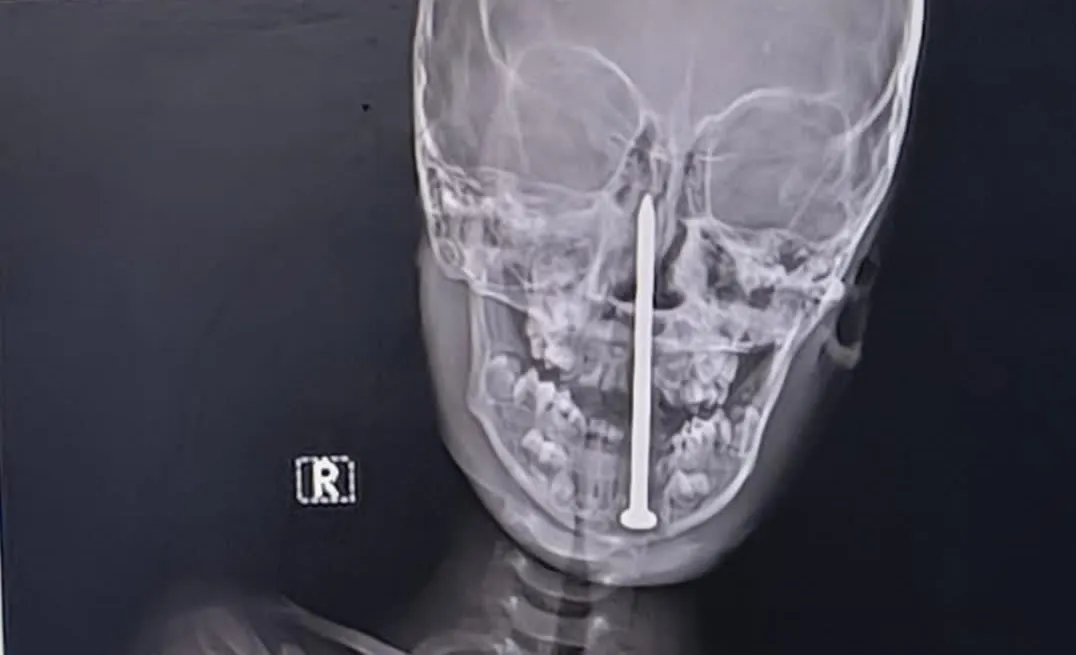

Deček med igro padel na osem centimetrov dolg žebelj, sledila zahtevna operacija |

V Indiji se je zgodila grozljiva nesreča. Sedemletni deček je med igro padel na osem centimetrov dolg žebelj, ki mu je prebodel glavo. Sledila je zaht